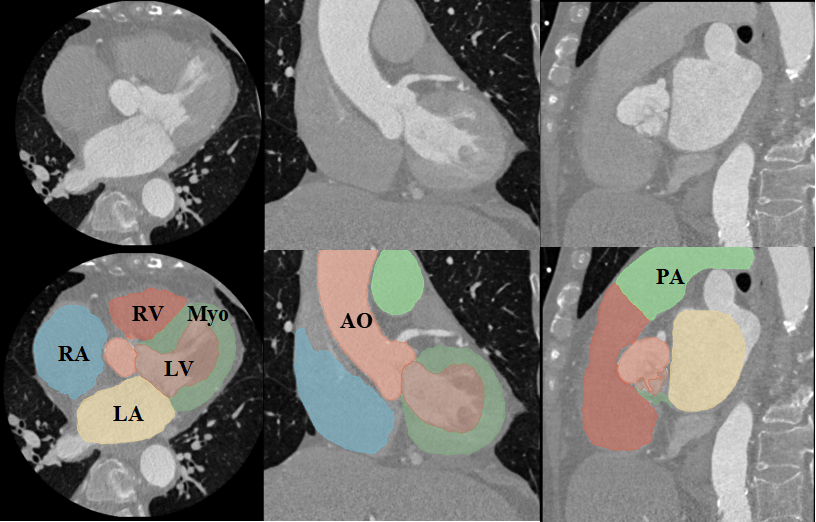

Figure 1: Examples of cardiac images and WHS results: (a) displays the three orthogonal views of a cardiac CT image and its corresponding WHS result, (b) shows example cardiac MRI data and the WHS result. LV: left ventricle; RV: right ventricle; LA: left atrium; RA: right atrium; Myo: myocardium of LV; AO: ascending aorta; PA: pulmonary artery.

In recent decades, significant advances in cardiovascular disease (CVD) research and practice have been made to improve the diagnosis and treatment of heart disease [1]. Cardiac image segmentation is an important first step in many applications. It partitions the image into several semantically (i.e., anatomically) meaningful regions, based on which quantitative measures can be extracted, such as the myocardial (Myo) mass, wall thickness, left ventricle (LV), right ventricle (RV) volume, left atrium (LA), right atrium (RA), ascending aorta (AO) or the whole aorta, and the pulmonary artery (PA)[23, 22], as Fig. 1 shows. Despite its wide range of applications, automated WHS remains challenging, e.g., systole and diastole of the heart, deformation of the heart’s shape from pathological and physiological changes, as well as differences in image acquisition equipment and motion artifacts that appear in the clinical data. State-of-the-art deep segmentation methods[12, 8, 16, 18, 10, 24, 5, 21] can automatically learn robust feature representations with satisfactory performance. However, standard deep neural networks cannot learn global structural constraints on semantic labeling, which is often crucial in the biomedical domain. For example, in WHS segmentation, we know in advance that Myo always encloses LV, and another global constraint is mutual exclusion for different labels.